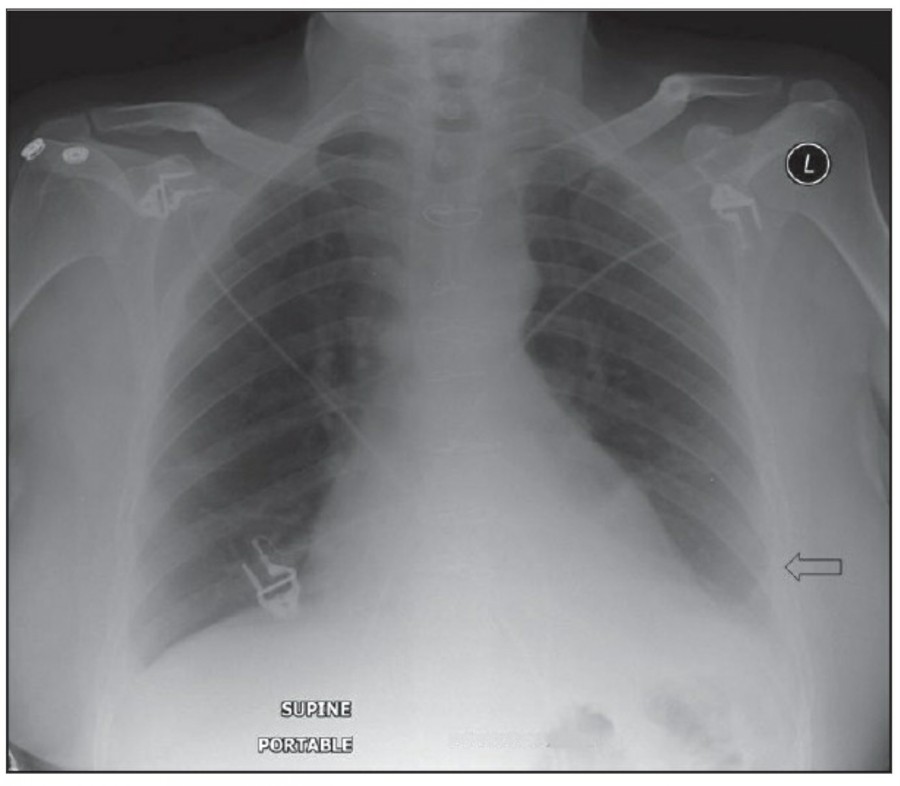

중환자실에서 일반적으로 PA chest X ray는 거의 시행하지 않으며, 주로 AP(anteroposterior) chest X ray를 시행한다. AP CXR은 upright position에서 최대 흡기 시 patient-to-x-ray plate가 72inches(182.88cm)지만, 중환자는 움직임이 제한되므로 supine 혹은 sitting position에서 시행하며 그 거리는 40inches(101.6cm) 정도다.

이렇게 얻어진 image는 gravitational and geometrical effect로 인해 mediastinum과 heart가 확대되어서 보이는데, 더욱이 supine position은 pulmonary vasculature의 physiology를 변화시켜서 혈류가 lung apex로 흐르게 한다-이렇게 얻어진 형태는 PA CXR에서는 비정상으로 간주되지만 AP CXR에서는 정상이다. Supine position은 pleural effuson과 air space shadowing의 감별, pneumothorax 발견을 힘들게 한다.

중환자는 협조가 되지 않거나 수술 후 통증 때문에 full inspiration이 쉽지 않으므로 X ray image를 얻기가 어렵다., 따라서 basialr atelectasis와 pulmonary edema의 진단이 어렵고, heart와 mediastinum의 크기가 정확히 나타나지 않게 된다.

Thoracotomy를 시행받고 나온 환자의 initial postoperative chest X ray에서 각종 line과 endotracheal tube, thoracotomy tube, mediastinal drains, central venous catheter 등을 확인할 수 있을 것이다. 이러한 device들은 그 위치가 제대로 있는지 확인해야 한다.

CABG를 받은 환자에서 lower lobe atelectasis는 흔한데, 주로 왼쪽에 잘 나타나며 수일 내에 별다른 합병증 없이 회복된다. mediastinum도 약간 확대되어 보일 수 있는데, 만약 그 diameter가 많이 증가한다면 mediastinal hemorrhage 등을 시사할 수 있다. CABG 시행 후 약간의 좌측 pleural effusion은 있을 수 있지만 그 양이 많거나 증가한다면 respiratory compromise를 줄이기 위해 intervention이 필요할 수 있다. 따라서 이전의 사진과 비교를 해서 pleural effusion 양의 변화가 있는지 확인이 필요하겠다.